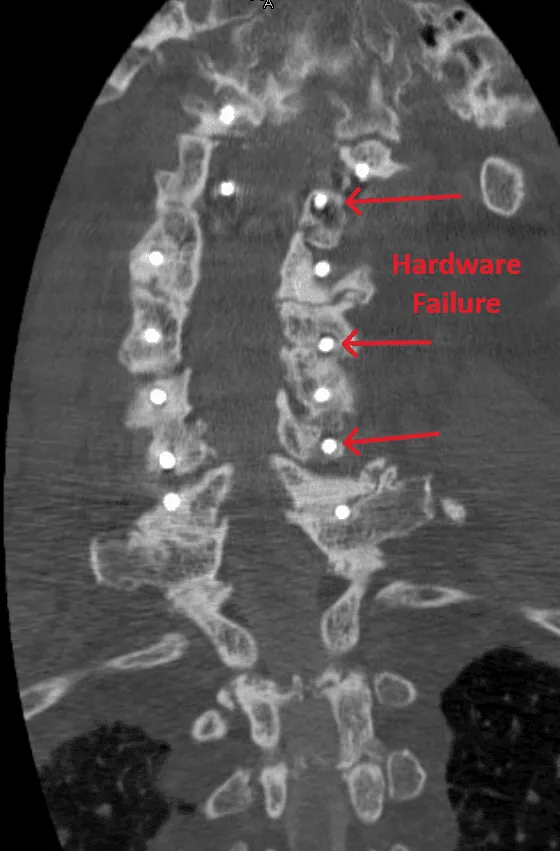

Hardware Failure

Screw loosening, broken screws or rods, and cage migration requiring revision surgery.